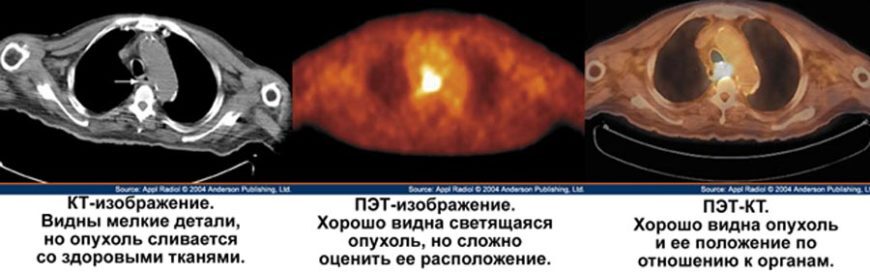

И ПЭТ — один из главных борцов с раком и Альцгеймером. Он видит не просто орган, а как он работает, где прячутся прожорливые раковые клетки. Звучит круто? Ага, только вот беда: картинка часто получается... как через грязное стекло во время дождя. Размыто. Шумно.

Можно запросто пропустить мелкую опухоль или перепутать ее со здоровой тканью. Печаль? Боль? Дорогое лечение? Всё вместе. И виноваты в этом не врачи, а законы физики. Вернее, наше недопонимание этих законов.

Детекторы томографа ловят эти фотоны и по точкам их прихода строят 3D-карту. Где ярче — там и подозрительная активность, потенциальная опухоль.